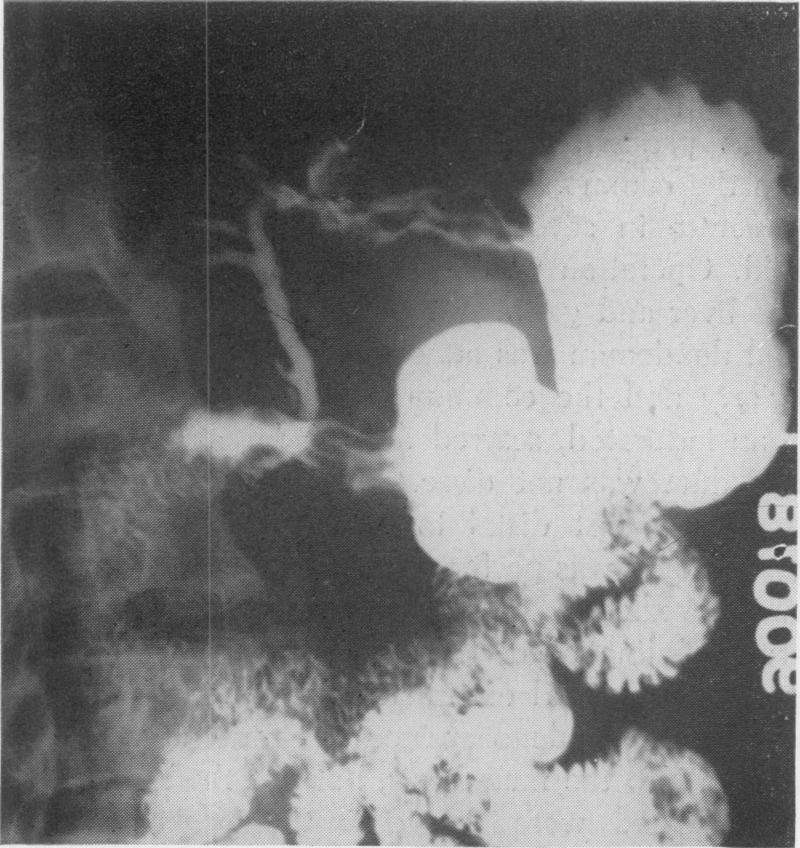

Choledochoduodenal fistula: its surgical management, including a report of three cases.

Ann Surg. 1954 Apr;139(4):510-6. doi: 10.1097/00000658-195404000-00018.